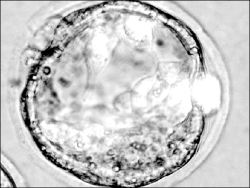

Madrid, 31 de octubre. Críticas de la Iglesia católica y aplausos de la comunidad científica acogieron el decreto del gobierno español que regula la investigación con células madres embrionarias, que posibilitará la cura de enfermedades como el Alzheimer, el Parkinson y la diabetes.

La vicepresidenta primera del gobierno, María Teresa Fernández de la Vega, y la ministra de Sanidad, Elena Salgado, presentaron el decreto aprobado el viernes en consejo de ministros ordinario, como un "paso importante" en la batalla contra enfermedades hoy por hoy incurables.

Siguiendo el ejemplo de países como Gran Bretaña o Suecia, España contará con dos centros pioneros. El Centro de Medicina Regenerativa de Barcelona existirá jurídicamente este mismo mes de noviembre para poder poner en marcha luego un Banco de Líneas Celulares en Granada.

La Federación de Asociaciones para la Defensa de la Salud Pública señaló que la medida es un "paso adelante" que permitirá colocar a España al frente de la investigación internacional de las células.